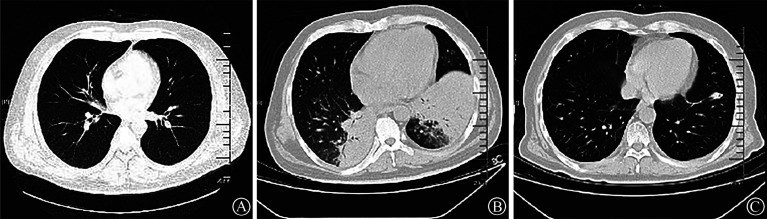

[Legionella infection complicating acute lymphoblastic leukemia: a case report].

[军团菌感染并发急性淋巴细胞白血病1例]。